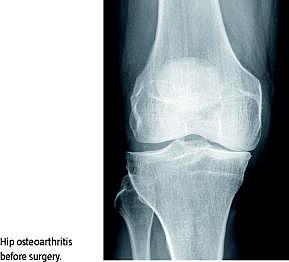

Tobaksforbrug, overvægt og indtagelse af alkohol har betydning for risikoen ved større operationer både set i relation til alvorlige komplikationer og i forhold til risikoen for mindre komplikationer som eksempelvis dårligere sårheling. Præoperativ reduktion af risikofaktorer kan derfor nedsætte operationsrisikoen. Fast track -operationsforløb med multimodal smertebehandling og hurtig mobilisering af patienterne efter operation har potentialet til at nedsætte risikoen for komplikationer, men det er uvist, i hvilket omfang en præoperativ reduktion af risikofaktorer yderligere kan nedsætte risikoen for komplikationer ved indsættelse af kunstigt hofte- eller knæled i et fast track -forløb. Formålet med dette studie var derfor at identificere risikofaktorer ved hjælp af et simpelt spørgeskema og at se, om en præoperativ screening med efterfølgende forsøg på intervention mod risikofaktorer kunne nedsætte antallet af komplikationer ved indsættelse af kunstigt hofte- eller knæled i et fast track -forløb.